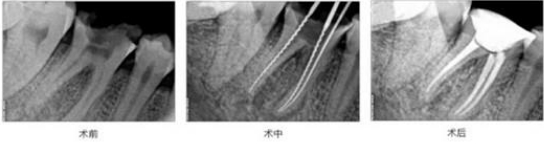

二、根管治疗+牙冠修复 已经伤及到牙髓的牙齿,常伴有剧烈疼痛,一般伴有牙髓炎,需进行根管治疗,一般待根管治疗后,为了防止牙齿折裂,并延长牙齿的使用寿命,好戴个牙冠加以保护。蛀牙已经龋坏的不能再保留了,采建议拔除后再镶牙,一般能治疗的尽量治疗,不能治疗的才建议拔除。

中诺口腔3D智能显微根管治疗采用多种智能治疗仪器,使治疗全程精确可控,更微创、更干净彻底。显着的3D立体效果,超大的景深,便于医生确切临床诊断清理根管内坏死物质和病菌,避免遗漏,是一种更有利于防止发生根尖周或促进根尖周愈合的一种治疗方式 。